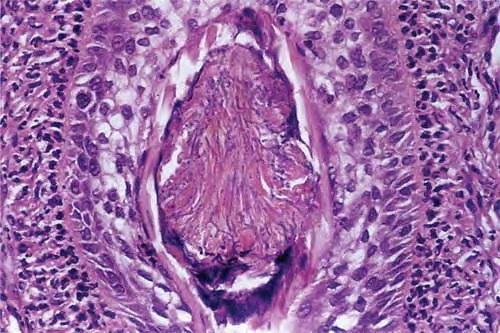

majoccchi-granuloma